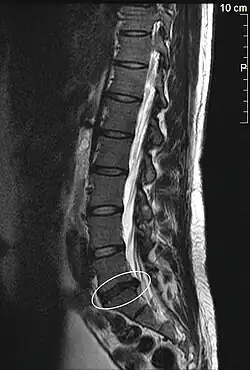

Lendenwirbelsäule

Als Lendenwirbelsäule (LWS) wird der in Höhe der Lende (lateinisch lumbo) gelegene, lumbale Teil der Wirbelsäule bezeichnet. Dieser Abschnitt besteht beim Menschen aus 5 Wirbeln, die als Lendenwirbel bezeichnet werden.

Beim Menschen wird die Lendenwirbelsäule durch den aufrechten Gang hoch belastet, sie stellt die Basis des Rumpfes dar. Durch diese Belastungen kommt es häufig zu schmerzhaften Reizzuständen. Der Oberbegriff „Kreuzschmerz“ mag dazu dienen, vom Schmerzsyndrom bis zum Bandscheibenschaden mit Ischialgien bzw. Lumbago oder auch neurologischen Ausfällen eine große Palette von Krankheitsbildern zusammenzufassen. Eine schwache Stützkraft im Lendenwirbelbereich kann sich bei Babys als Sitzkyphose zeigen. Form und Aussehen der Lendenwirbelsäule unterliegen beim Menschen einer großen Variabilität. Dies lässt die Annahme zu, dass die Anpassungen an die mit der entwicklungsgeschichtlich jungen Bipedie verbundenen aufrechten Körperhaltung in Stand und Gang womöglich noch nicht abgeschlossen sind.